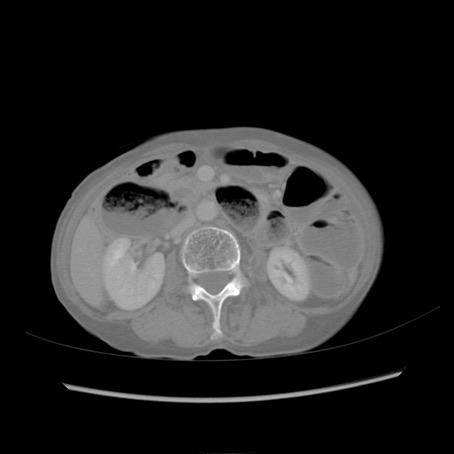

症例25(横断像)

【症例】80歳代女性

【主訴】胸のつかえ感

【現病歴】約9時間前に食後から胸のつかえた感じあり、嘔吐あり、来院。

【既往歴】胃癌(全摘)、胆摘、虫垂炎

【身体所見】心窩部に圧痛あり、反跳痛なし。

【データ】WBC 5700、CRP 0.05